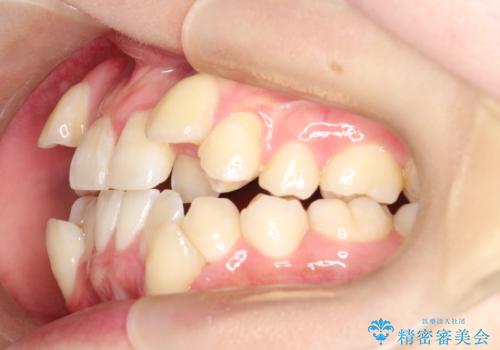

【ワイヤー矯正】八重歯 歯のでこぼこを治したい!

- 治療計画

- 「歯のでこぼこを治したい」を主訴に来院された患者様です。 上下ともに、歯のでこぼこが強く、上下左右4の抜歯をし、ワイヤー矯正で治療を行いました。

かなり綺麗に並ぶ事ができ大変満足していただけました。

叢生量がかなり多かったのですが、歯肉退縮も失活歯も無くとても綺麗な歯並びになりました。